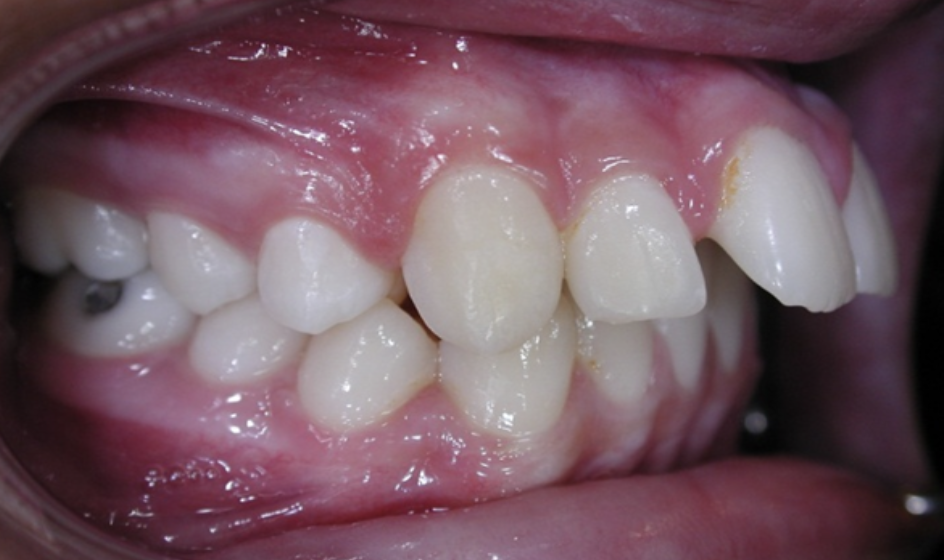

Protrusion

Upper teeth stick out beyond the lower teeth.